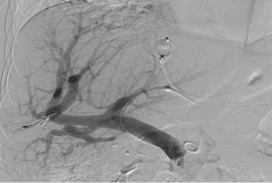

2023 London Imaging Discovery Day